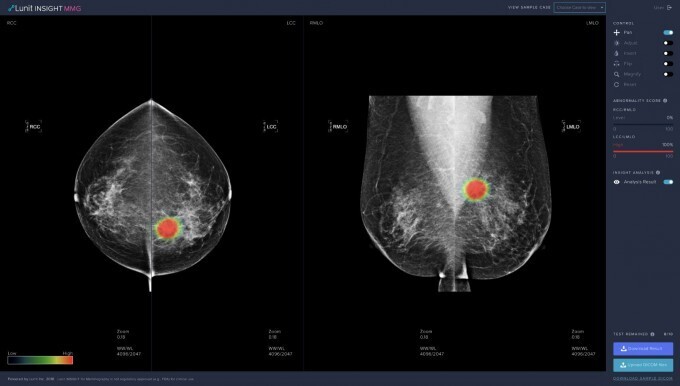

국내 첫 의료AI 스타트업으로 지난 2013년 설립된 루닛은 이달 1일 노벨 생리의학상 수상자를 선정하는 스웨덴 왕립 카롤린스카연구소가 진행한 유방암 진단 AI 비교 연구에서 최고 평가를 받았다. 유방암을 정확하게 찾아내는 민감도 지표가 81.9%로 의사들의 77.4%보다 높은 것으로 분석됐다. 또 다른 국내 스타트업인 뷰노는 흉부 엑스레이 영상 판독 AI가 서울아산병원 건강증진센터에서 활용되기 시작, 인공지능 AI와 전문의가 함께 진단을 결합하면 정확도는 더 높아진다

유방암 검진을 위한 구글의 인공지능(AI) 모델을 의료 이미징 시스템에 통합하기 위해 의료 기술 회사인 아이캐드(iCAD)와 구글이 계약을 체결했다. 이는 구글의 유방조영술 AI 모델에 대한 첫 라이선스 및 상용화 계약이어서 주목된다. 구글은 이 기술을 실제 임상에 적용할 예정이며 아이캐드의 기술은 미국 전역과 전 세계 7500여 개의 의료 시스템 및 이미징 센터에서 사용된다. 구글의 유방 조영술 AI 연구 모델을 아이캐드의 기존 도구에 통합할 계획으로 첫 번째는 3D 유방 조영술이라고도 하는 고급 이미징 기술인 DBT(디지털 유방 합성법)의 이미지를 분석하는 프로 파운드 AI(ProFound AI) 도구다

이 도구는 악성 연조직 밀도 및 석회화를 찾기 위해 DBT 이미지를 스캔한다. 아이캐드는 또한 위험 평가 도구에도 구글의 모델을 사용한다. 구글은 2018년에 영국 및 미국의 임상 연구 파트너와 협력하여 유방암 진단을 개선하기 위한 AI 모델을 테스트하기 시작했고 이 2020년 네이처 저널에 자사의 AI 모델이 유방암 징후를 식별하는 데에서 방사선 전문의를 능가한다는 논문을 발표한 바 있다. 이 논문은 위양성(false positive)을 최대 5.7%, 위음성(false negative)을 최대 9.4%까지 줄일 수 있었다는 초기 연구 결과를 공유했다.